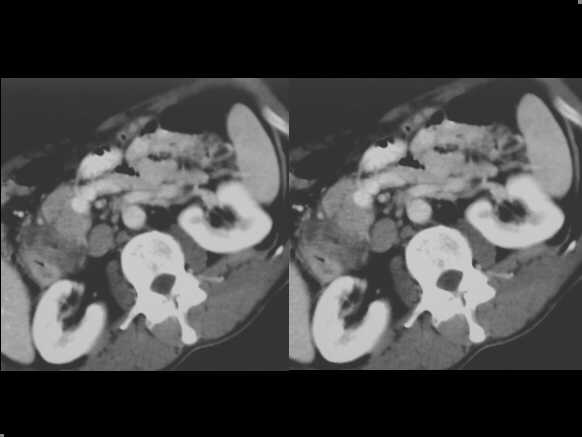

Focal autoimmune pancreatitis of the head. Spiral CT examination, before and after c.m. administration, demonstrates an enlarged head, which appears hypodense in the arterial contrastographic phase towards the spleen. Hypodensity remains appreciable in the venous phase.